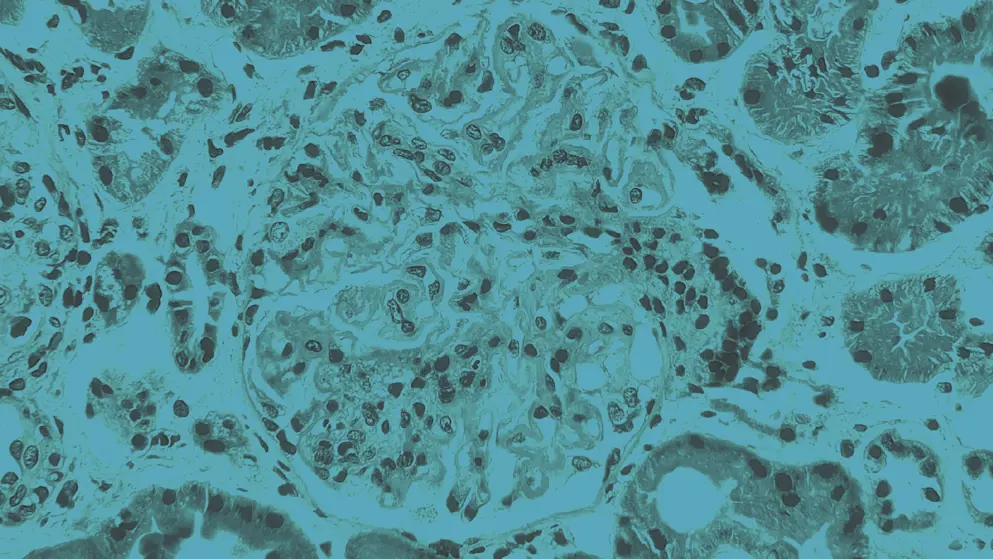

Cystinosis is a rare autosomal recessive disorder caused by mutations in the CTNS gene, which impair lysosomal cystine transport. The condition presents in three forms – infantile nephropathic, juvenile nephropathic, and ocular non-nephropathic – each varying in severity and age of onset. Intracellular cystine accumulation leads to crystal formation that progressively damages multiple organ systems, particularly the renal, ocular, endocrine, and muscular systems.